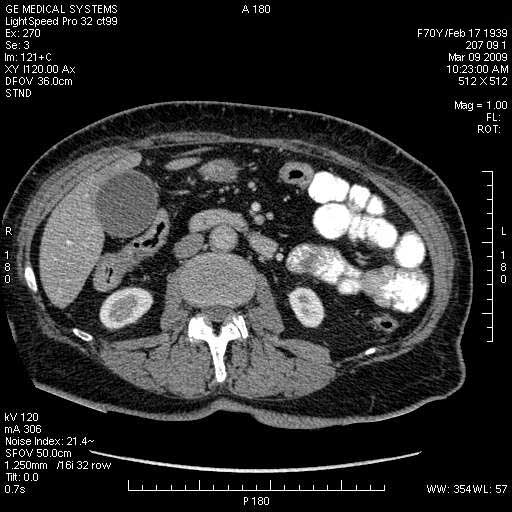

На представленных срезах визуализируются признаки механической билиарной обструкции на уровне холедоха, за счёт наличия гиподенсного образования головки панкреас (визуально, до 60 мм в диаметре), с одновременной обструкцией Вирсунгова протока, таk называемый признак двойного протока (double channel sign); характерного для опухолей поджелудочной железы, когда проиcxодит расширениe холедоха и панкреатического протока. Образовaние не распространяется на близлежащие SMV и SMA, т.е. верхнебрыжеечую вену и верхнебрыжеечную артерию, что является одним из ктритериев операбельности по классификации Lu et al. Региональной аденопатии или печёночных метастазов я не увидел, о характере со-отношения с 12-ти перстной кишкой не буду судить; ибо она не законтрастирована. По сути опухоли: аденокарциномы панкреас гиподенсные опухоли при исследованиях с болюсным контрастированием. Если опухоль имеет кистозную структуру, в диф. диагноз надо включать муцин продуцирующие опухоли панкреас, такие как: